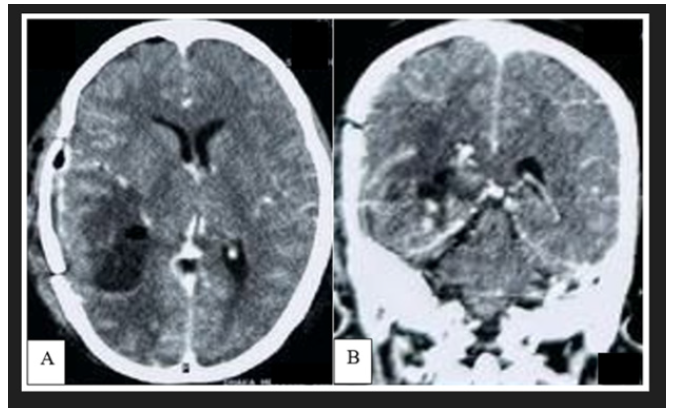

CT scan of brain demonstrated a well circumscribed hyperdense extra-axial lesion in posterior part of right temporal lobe, having attachment with part of tentorium cerebelli. The mass was surrounded by moderate vasogenic edema with no features of calcification (Figure 2). Computed tomography of the chest, abdomen, and pelvis was performed to look for any systemic involvement and was unremarkable. Brain Magnetic Resonance Imaging (MRI) showed a lobulated lesion of about 5x 4.7x 4cm diameter which was predominantly hyperintense in T1WI, intensely hypointense with a central isointese signal change in T2WI (Figure 3A,3B). After administration of gadolinium, there was intense heterogenous contrast enhancement owing to its high vascularity (Figure 3C). The lesion also exhibited similar hypointense signal change in FLAIR sequence with no restricted diffusion in DWI. Mass effect was evidenced by flattening of surrounding sulci and gyri with mild midline shifting. However, there were no features of hydrocephalus and similar lesion elsewhere in the brain (Figure 3D-3F) (Figure 3).

Figure 2: Preoperative non contrast CT scan of brain demonstrated a well-defined hyperdense lesion in right temporo-parietal region, surrounded by moderate perilesional edema with mass effect.

The diagnostic value of CT in tumors presenting as isodense or hyperdense lesions is poor [4]. Our reported case showed a well-defined hyperdense lesion in the right temporal lobe and this hyper density was due to the presence of intra-tumoral hemorrhage (Figure 2). Melanocytes are paramagnetic; because of this, both T1 and T2 relaxation times are shortened and thus hyperintense on T1-weighted images and hypointense on T2-weighted images [25,6]. The diamagnetic feature (calcification) and paramagnetic features (hemosiderin) would produce signal dropout and blooming, respectively, on susceptibility-weighted images. Phase-filtered images may also help differentiate hemosiderin-containing calcifications in meningioma versus microhemorrhages in melanoma, as calcifications will appear hyperintense from a negative phase shift, while hemosiderin will show loss of signal from a positive phase shift [26]. Rarely, melanoma might have both solid and cystic component where they can demonstrate heterogenous signal intensity in all sequences [14,15]. Beside this, intratumoral hemorrhage of different ages can exhibit heterogenous signal change too which can bias the radiologist with another hemorrhagic intracranial tumor [27]. Our reported case demonstrated similar features with an additional presence of dural tail which mimics the diagnosis of tentorial meningioma (Figure 3). Besides this, multiple linear high-intensity regions can be observed on the surface, within cerebral fissures or sulci which indicates leptomeningeal spreading. However, this pattern of enhancement is not pathognomonic for leptomeningeal melanosis and can be observed in infectious, inflammatory, and leptomeningeal carcinomatosis of the central nervous system. [12].